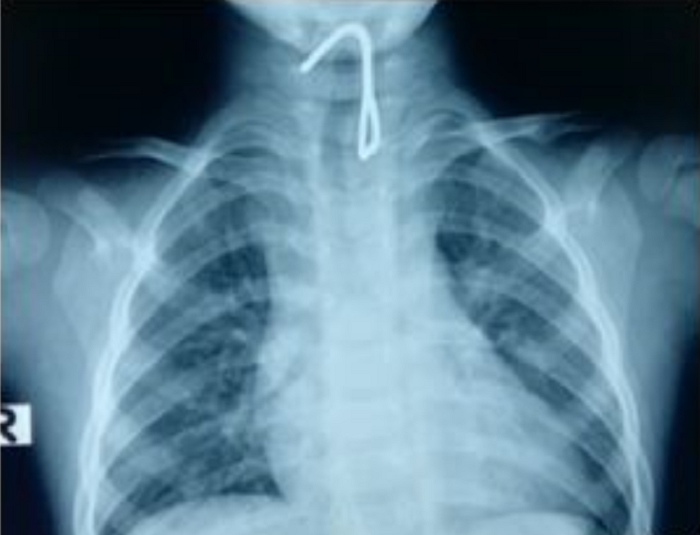

Khi đến khám tại BV địa phương và được chụp X-quang, kết quả X-quang cho thấy bé có khả năng mang dị vật cản quang vùng thực quản nên được chuyển đến bệnh viện (BV) Nhi Đồng 1 (TP.HCM).

Chiếc móc sắt nằm gọn trong thực quản bé.